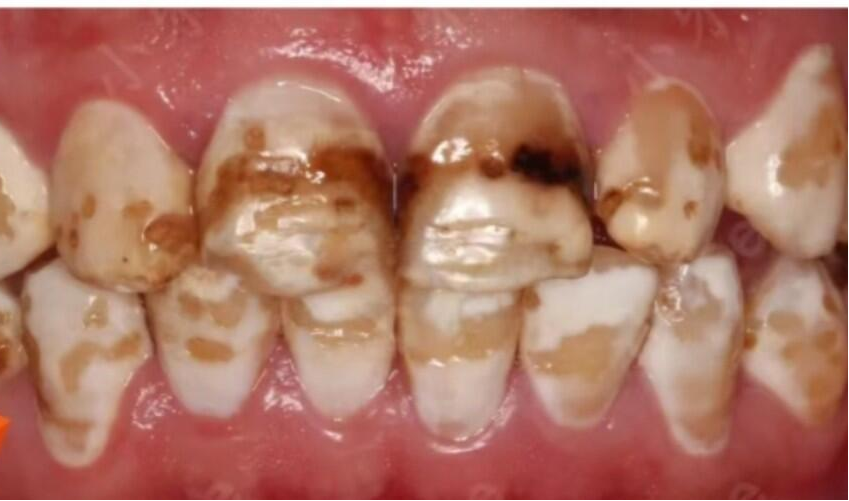

氟斑牙的影响程度不一,主要分为以下三种情况:

1.轻度(白垩型): 牙面上出现不透明的黄白相间的斑块或条纹,表面粗糙。

2.中度(着色型): 牙齿表面出现黄褐色或棕色的斑块,影响美观,但牙体形态没有明显缺损。

3.重度(缺损型): 除了严重的颜色改变,牙釉质还会出现凹凸不平的坑洼、缺损,甚至可能引发牙齿敏感。